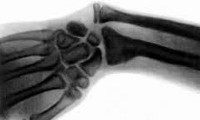

Врожденная косорукость. Устойчивая деформация, в результате которой кисть отклоняется в локтевую либо лучевую сторону от продольной оси предплечья. Возникает во внутриутробном периоде. Является следствием недоразвития одной из костей предплечья либо ассоциированных с этими костями сухожилий. Проявляется искривлением верхней конечности - кисть расположена под углом к предплечью. Может сочетаться с недоразвитием пястных костей, фаланг пальцев, отсутствием одного или нескольких пальцев, сращением пальцев, контрактурами, подвывихами либо вывихами в локтевом и лучезапястном суставах. Диагноз выставляется на основании рентгенологической картины и данных объективного исследования. Лечение хирургическое, проводится в раннем возрасте (обычно до 1 года). После операции назначается ЛФК, массаж и физиотерапия.

Постановка диагноза врожденная косорукость не представляет затруднений из-за визуально видимых деформаций и явных нарушений функции конечности. Для точной оценки степени недоразвития костных структур и уточнения дальнейшего плана лечения выполняют рентгенографию костей предплечья и рентгенографию костей кисти. Для оценки состояния мягких тканей назначают МРТ предплечья и электромиографию.